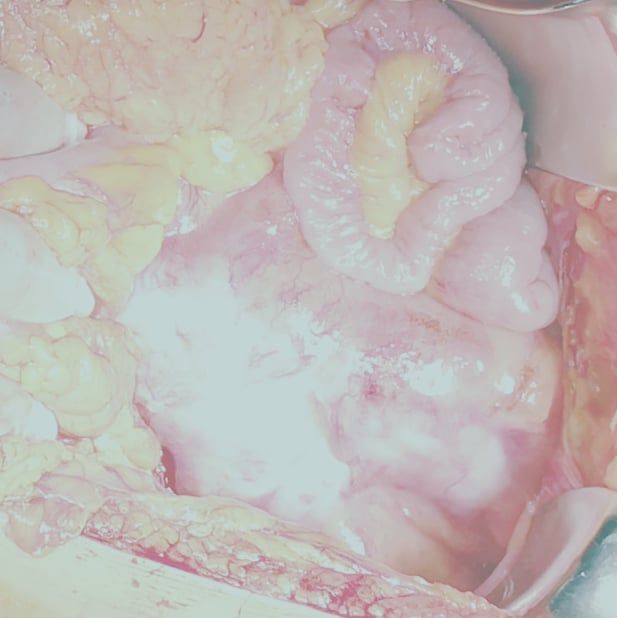

Fotos y videos